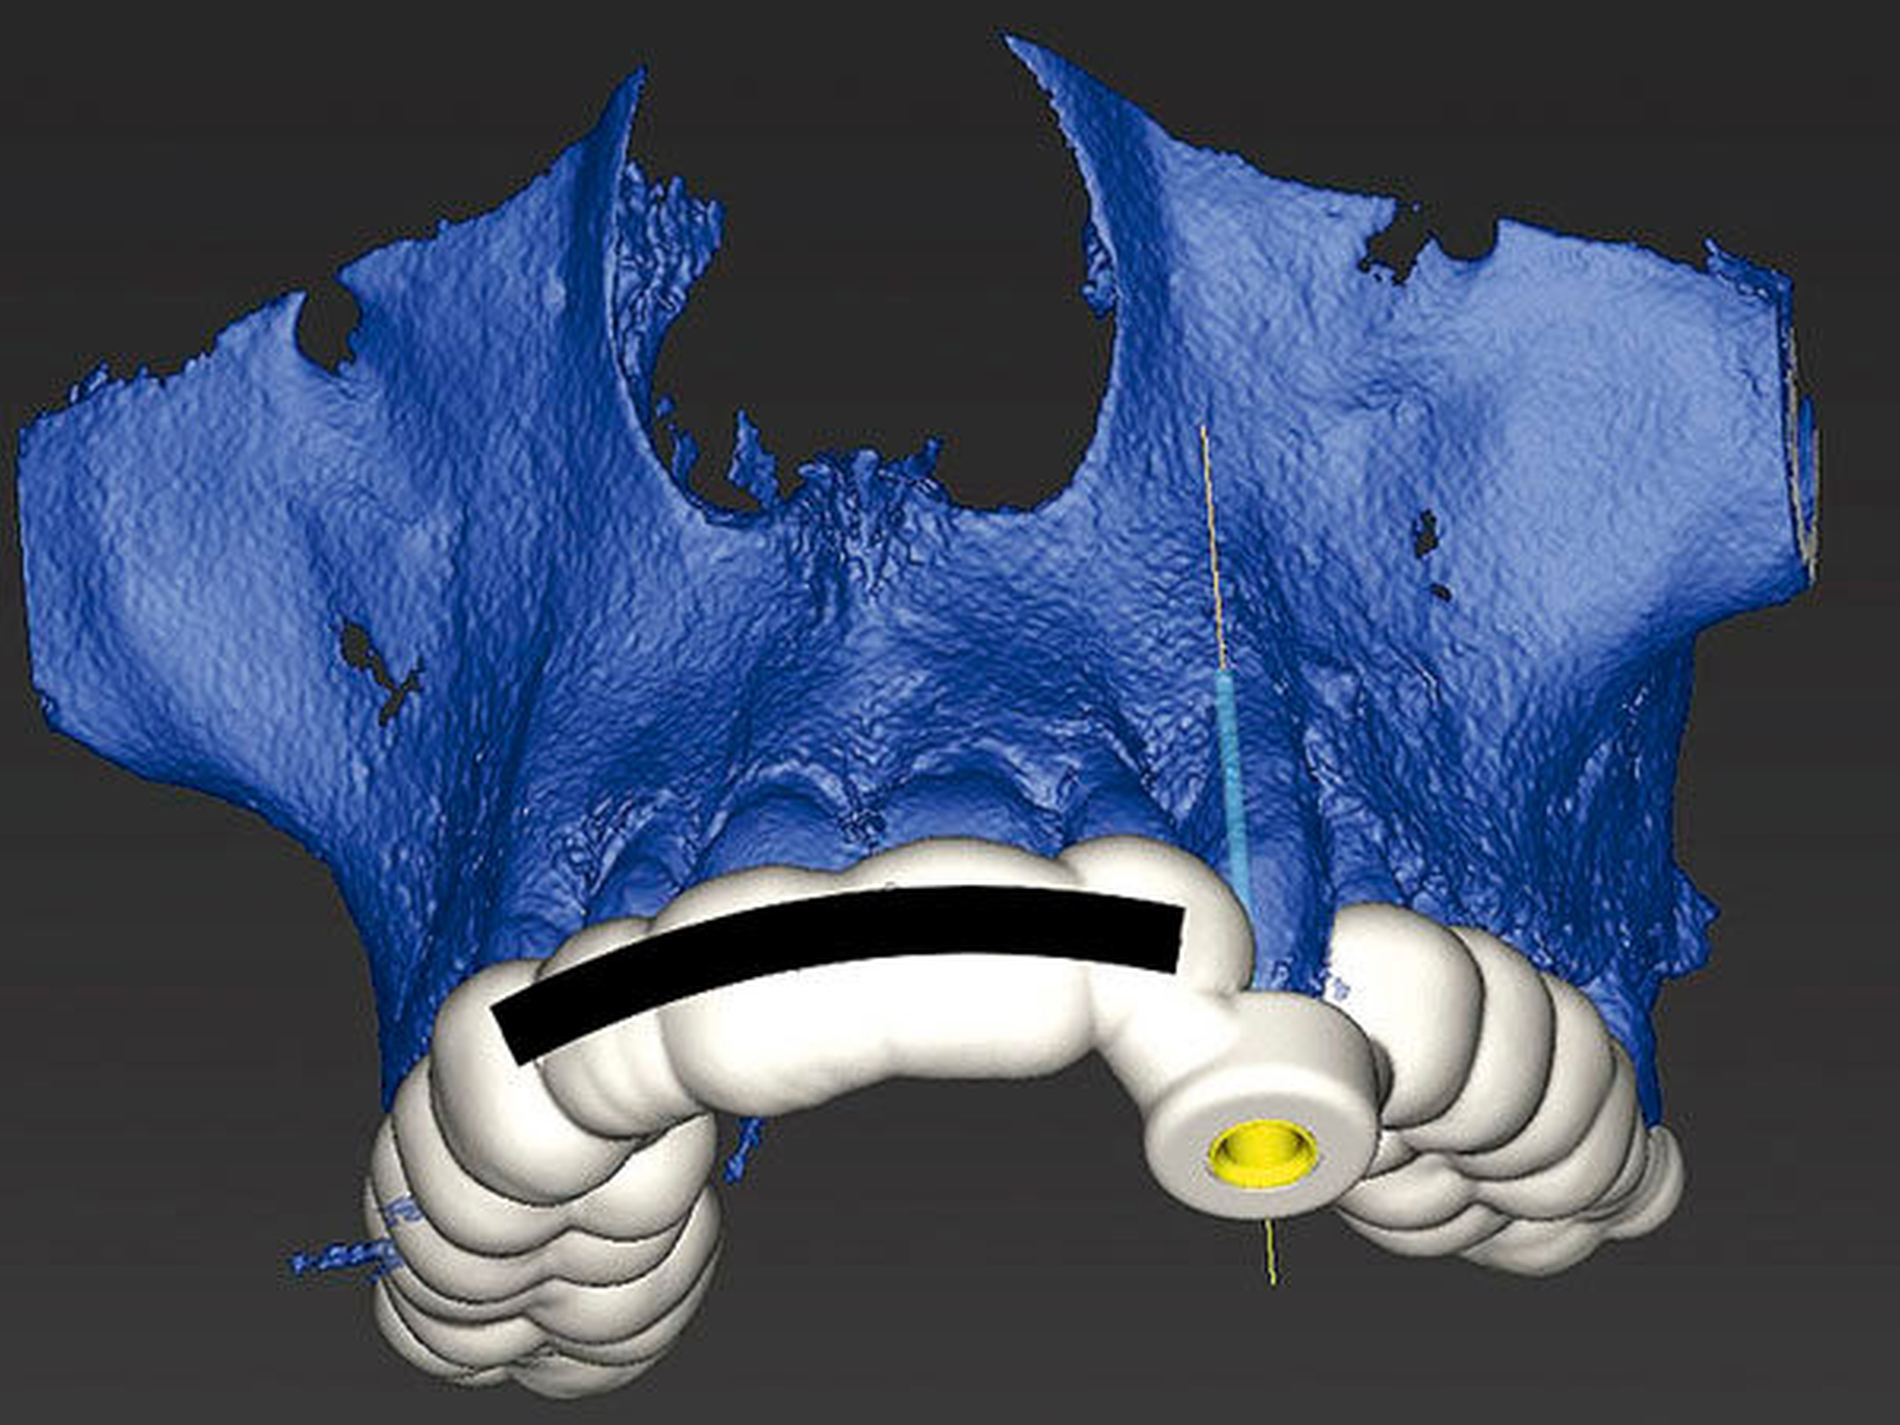

Zunächst wurde hierfür eine DVT–Aufnahme mit einem FOV von 8 cm x 8 cm angefertigt (Orthophos XG 3D, Sirona, Bensheim) und das Oberkiefer-Modell des Patienten gescannt (3Series Dentaler Modellscanner, Dental Wings, Montreal, Kanada). Die DICOM- und SLT-Datensätze wurden anschließend in die Planungssoftware (coDiagnostiX, Dental Wings, Montreal, Kanada) übertragen, fusioniert, und es wurde virtuell eine optimale Zugangskavität geplant. Der verwendete Endoseal-Bohrer (Atec Dental, Ebringen) mit einem Durchmesser von 1,0 mm sowie die auf den Bohrer abgestimmte Endo-Guide-Innenhülse (Steco Systemtechnik, Hamburg) sind in der Software hinterlegt. Bohrer und Hülse werden in der Software so positioniert, dass die Zugangskavität bis in die apikalen Kanalabschnitte erfolgen kann (Abbildungen 5 bis 7). Nach der virtuellen Planung (Abbildung 8) erfolgte die Herstellung der Navigationsschiene mit dem 3-D-Drucker Form 2 (Formlabs, Berlin). Im Anschluss wurde die Hülse in die Schiene eingesetzt (Abbildung 9).